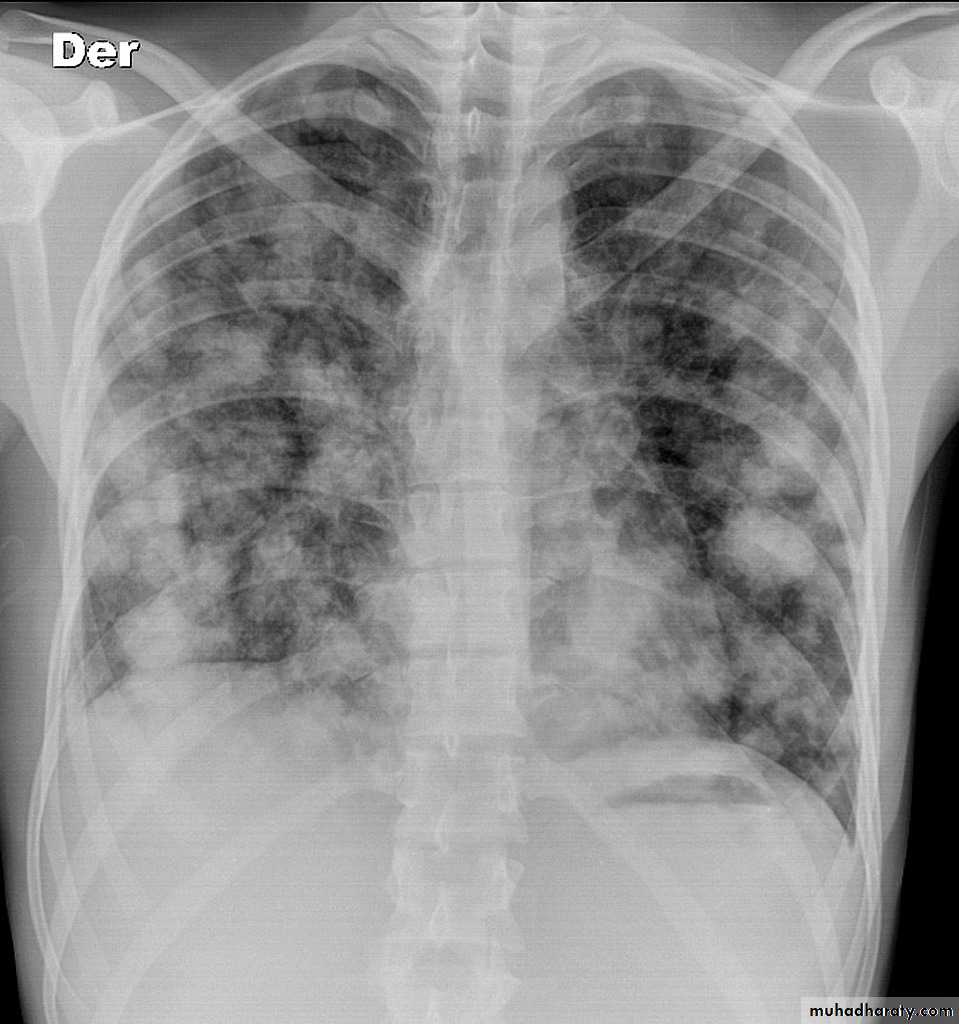

Pulmonary metastases are common and the result of metastatic spread to the lungs from a variety of tumors and can spread via blood or lymphatics.1.Cannonball metastases refer to large well circumscribed, round multiple opacities like cannonballs

2.lymphangitis carcinomatosis , is the term given to tumor spread through the lymphatics of the lung , and is most commonly seen secondary to adenocarcinoma Unfortunately up to a quarter of patients with subsequently established lymphangitic carcinomatosis have normal chest x-rays . When abnormal the most common finding is of a reticulonodular pattern, with thickening of the interlobular septae which may resemble Kerley B lines + /- pleural effusion .

3.innumerable small metastases (miliary pattern).